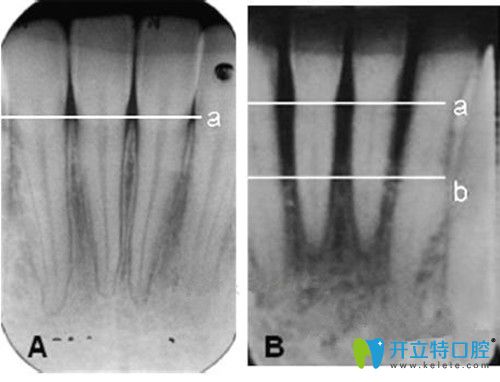

正常的牙槽骨和萎縮的牙槽骨